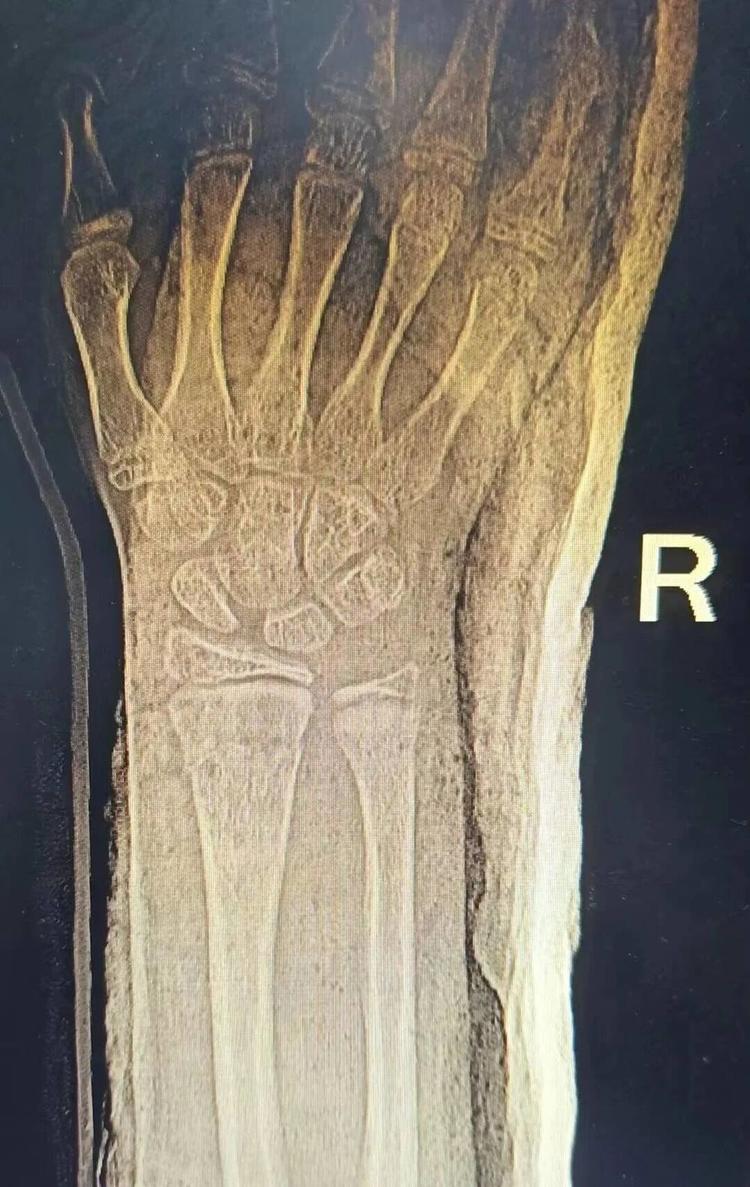

患者李某因意外造成桡骨远端骨折,若复位不佳,极易遗留腕关节畸形、疼痛无力等后遗症。来到益民中西医结合诊所后,通过陈氏正骨手法配合外用药治疗,复位效果理想。

▲治疗前后对比